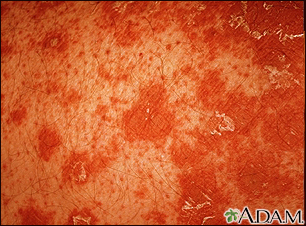

Pityriasis rubra pilaris - close-up

Pityriasis rubra pilaris is an uncommon skin condition. It is characterized by salmon-colored patches with scaling, clear areas of normal skin, and thick palms and soles. Hair follicles with keratin plugging is a characteristic sign. Typically the follicle is surrounded with a characteristic orange-red color.